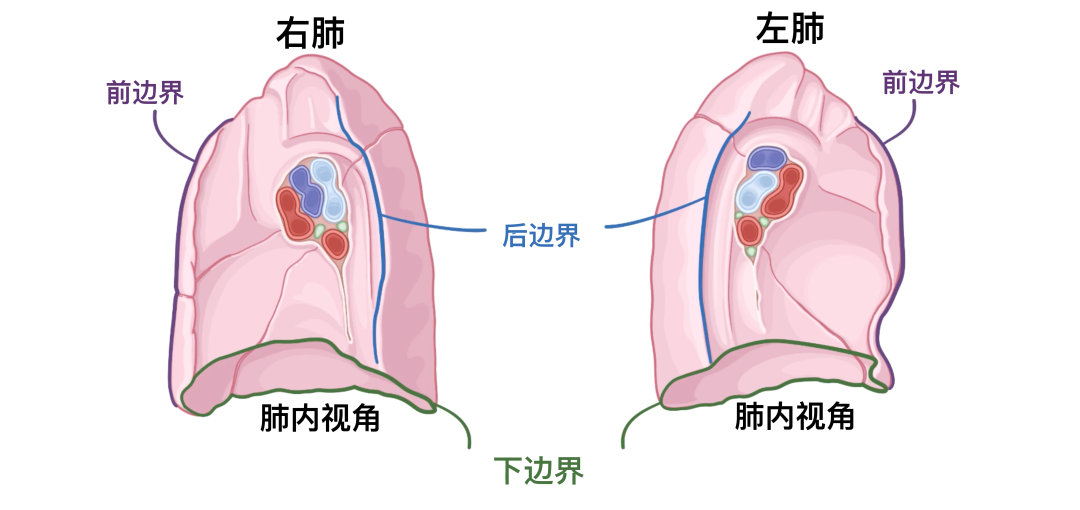

关于边界,前缘是肋表面和纵隔表面前面相交的地方。在右肺,它几乎是直的,而在左肺,它因心切迹而偏离。下缘薄而尖锐,界定肺的膈表面并将其与肋和纵隔表面分开。它还伸入胸膜的肋膈隐窝。后缘是肋面和纵隔面向后相交的地方,宽而圆形,位于脊柱胸椎区域的侧面。